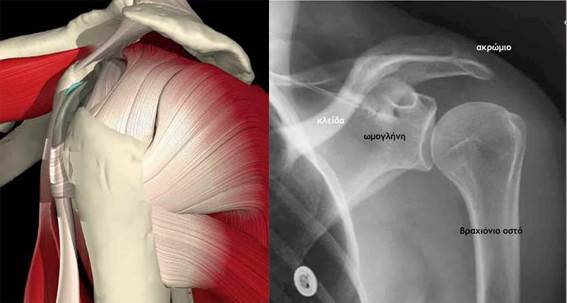

Κολυμβητικός ΏμοςΤο σύνδρομο περιλαμβάνει τα συμπτώματα και τα κλινικά σημεία, που οφείλονται στην προστριβή του μυοτενοντίου πετάλου των στροφέων του ώμου (ιδιαίτερα του τένοντα του υπερακανθίου) και του υπακρωμιακού ορογόνου θυλάκου, μεταξύ της κεφαλής του βραχιονίου (μείζονος βραχιονίου ογκώματος) και του ακρωμιοκορακοειδούς τόξου. Ιδιαίτερη κλινική οντότητα αποτελούν οι μεμονωμένες ρήξεις του υποπλατίου, που οφείλονται στην προστριβή του στην κορακοειδή απόφυση.

Το μυοτενόντιο πέταλο του ώμου σχηματίζεται από τη συνένωση των καταφυτικών τενόντων του υπερακανθίου, υπακανθίου, ελάσσονος στρογγύλου και υποπλατίου μυός. Οι τένοντες αυτοί, μαζί με τον τένοντα της μακράς κεφαλής του δικεφάλου βραχιονίου, σταθεροποιούν την κεφαλή του βραχιονίου στην ωμογλήνη. Το ακρωμιοκορακοειδές τόξο σχηματίζεται από το ακρώμιο, τον ακρωμιοκορακοειδή σύνδεσμο και την κορακοειδή απόφυση.